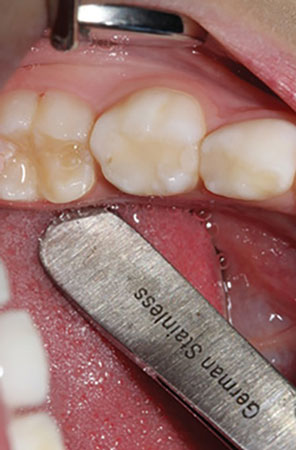

The following case study is presented to illustrate the ease of tooth preparation and crown cementation: A 5-year-old patient presented with caries of her primary dentition. The mandibular left primary molar required full coverage due to a failed composite restoration and extensive decay (figure 1). Both the child and her mother had a desire for a tooth-colored restoration. A primary prefabricated zirconia crown (NuSmile ZR) was chosen as the restorative material of choice.

Figure 1: Mandibular left primary molar